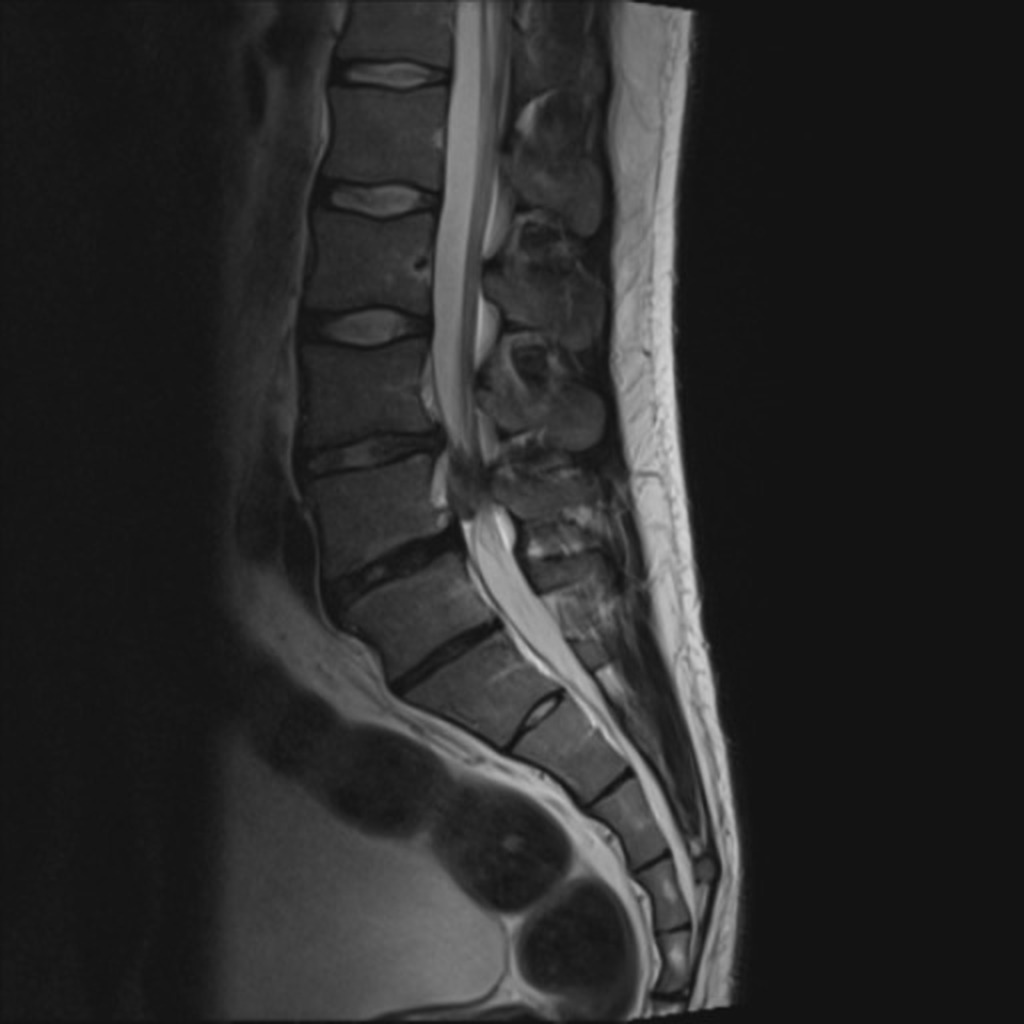

Beeldvorming

• NHG (2015) NA 6 weken in samenspraak met patiënt2